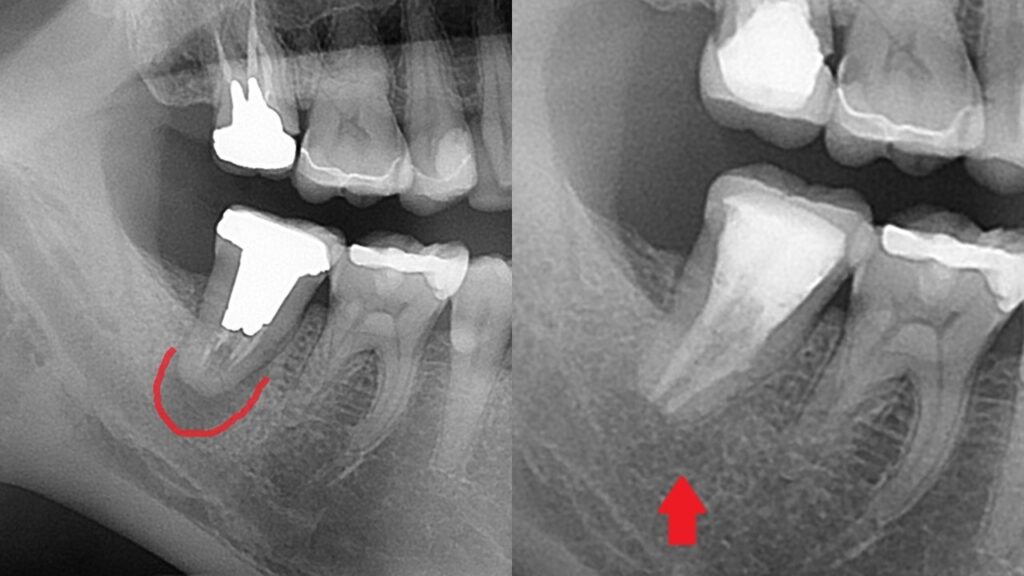

レントゲン写真を撮ってみると、

右下7番目の歯です。根っこの中に白いスジがあり、神経治療がされています。

そして、赤い枠の中が黒く抜けて見えます。膿で顎の骨が溶けています。

エックス線写真でも、黒い膿が無くなり、

周りの骨が均一に再生しています。

治療前後の比較です。